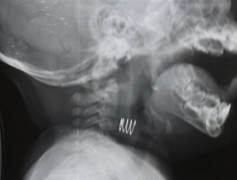

Bé trai 7 tuổi ở Vĩnh Long đang uống thuốc điều trị viêm họng mũi, người mẹ bất cẩn chưa kịp lột vỏ vỉ thiếc thì bé trai bỏ vào miệng nuốt phải cấp cứu.